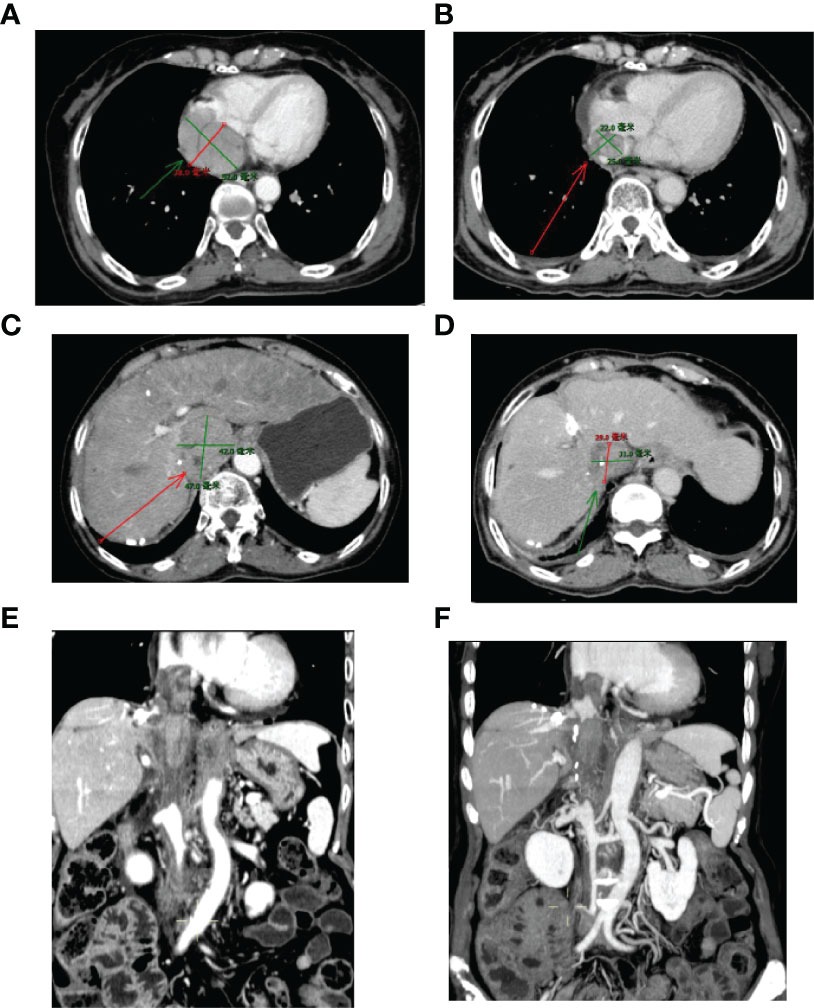

This case report was conducted per the CARE Guidelines (17). In July 2021, a 66-year-old Chinese woman was hospitalized due to severe bilateral lower extremity edema and palpitation, without any accompanying symptoms, such as abdominal pain or bloating. She had no history of high blood pressure, diabetes, or hepatitis. She had been diagnosed with HCC nine years ago and had undergone surgical resection. Postoperative pathology revealed a highly differentiated HCC. She had received radiofrequency ablation because of local HCC recurrence in November 2013 and May 2014. Subsequently, the patient did not undergo medical examination until July 2021. In July 2021, an enhanced computed tomography (CT) showed HCC recurrence at the junction of the anterior segment (S5/S8) of the liver, with approximately 1.8 × 1.4 cm size. The mass wrapped and invaded the adjacent IVC and grew into the IVC, RA, and left renal vein. The diagnosis was HCC with RA and IVC tumor thrombi with Barcelona clinic liver cancer (BCLC) stage-C (Figure 1). Then, the patient received sorafenib treatment and developed grade 4 (the US National Cancer Institute Common Terminology Criteria for Adverse Events [CTCAE v4.03]) skin rash and discontinued the sorafenib treatment. Hormones and proglobulin were used to treat dermatitis, and adverse skin reactions were reversed. According to a published study, radiotherapy can be used to treat liver cancer with RA and IVC tumor thrombi (18). Moreover, immunotherapy plus radiotherapy and antiangiogenic therapy is a safe and effective approach for advanced HCC (19). Therefore, we administrated radiotherapy, immunotherapy, and lenvatinib. The patient received radiotherapy in August 2021 through volumetric modulated arc therapy and respiratory gating technology. The dose for HCC recurrence was 50 Gy/25 fractions and for HCC with RA and IVC tumor thrombi was 45 Gy/25 fractions (Figure 2). She simultaneously received pembrolizumab (100 mg; 2 mg/kg, q3w) and lenvatinib (8 mg/day). Lower extremity edema and palpitations resolved after radiotherapy. Toxicity was well tolerated with no liver toxicity, and grade ≥ 3 adverse events were observed. After four cycles of pembrolizumab plus lenvatinib treatment, the CT scan indicated that the patient had a partial response and a decreased thrombus according to the Response Evaluation Criteria in Solid Tumors (RECIST) v.1.1. The HCC lesion at the junction of S5/S8 segment disappeared, and the IVC/RA thrombus decreased in size (Figure 3). No disease progression was observed. The patient continued to receive the pembrolizumab plus lenvatinib treatment (the last pembrolizumab treatment day was March 26, 2022). The patient remained stable at the time of writing (> 7 months). During the treatment period, there was no grade ≥ 3 adverse events or liver toxicity. Leukopenia (grade 2), thrombocytopenia (grade 1), hypoalbuminemia (grade 1), and hypertension (grade 2) were resolved using symptomatic drug treatment. Granulocyte colony-stimulating factor was administered to deal with white blood loss. A CT scan was regularly performed for every 3 months. Blood routine, liver function, kidney function, electrolyte, thyroid function, and pituitary function were regularly measured. The timeline scheme of the major clinical events of the patient since HCC diagnosis is shown in Figure 4.

Figure 3 Sizes of RA and IVC tumor thrombi before and after 3-month treatment. (A, C, E) Before treatment; (B, D, F) Three months after treatment. IVC, inferior vena cava; RA, right atrium.